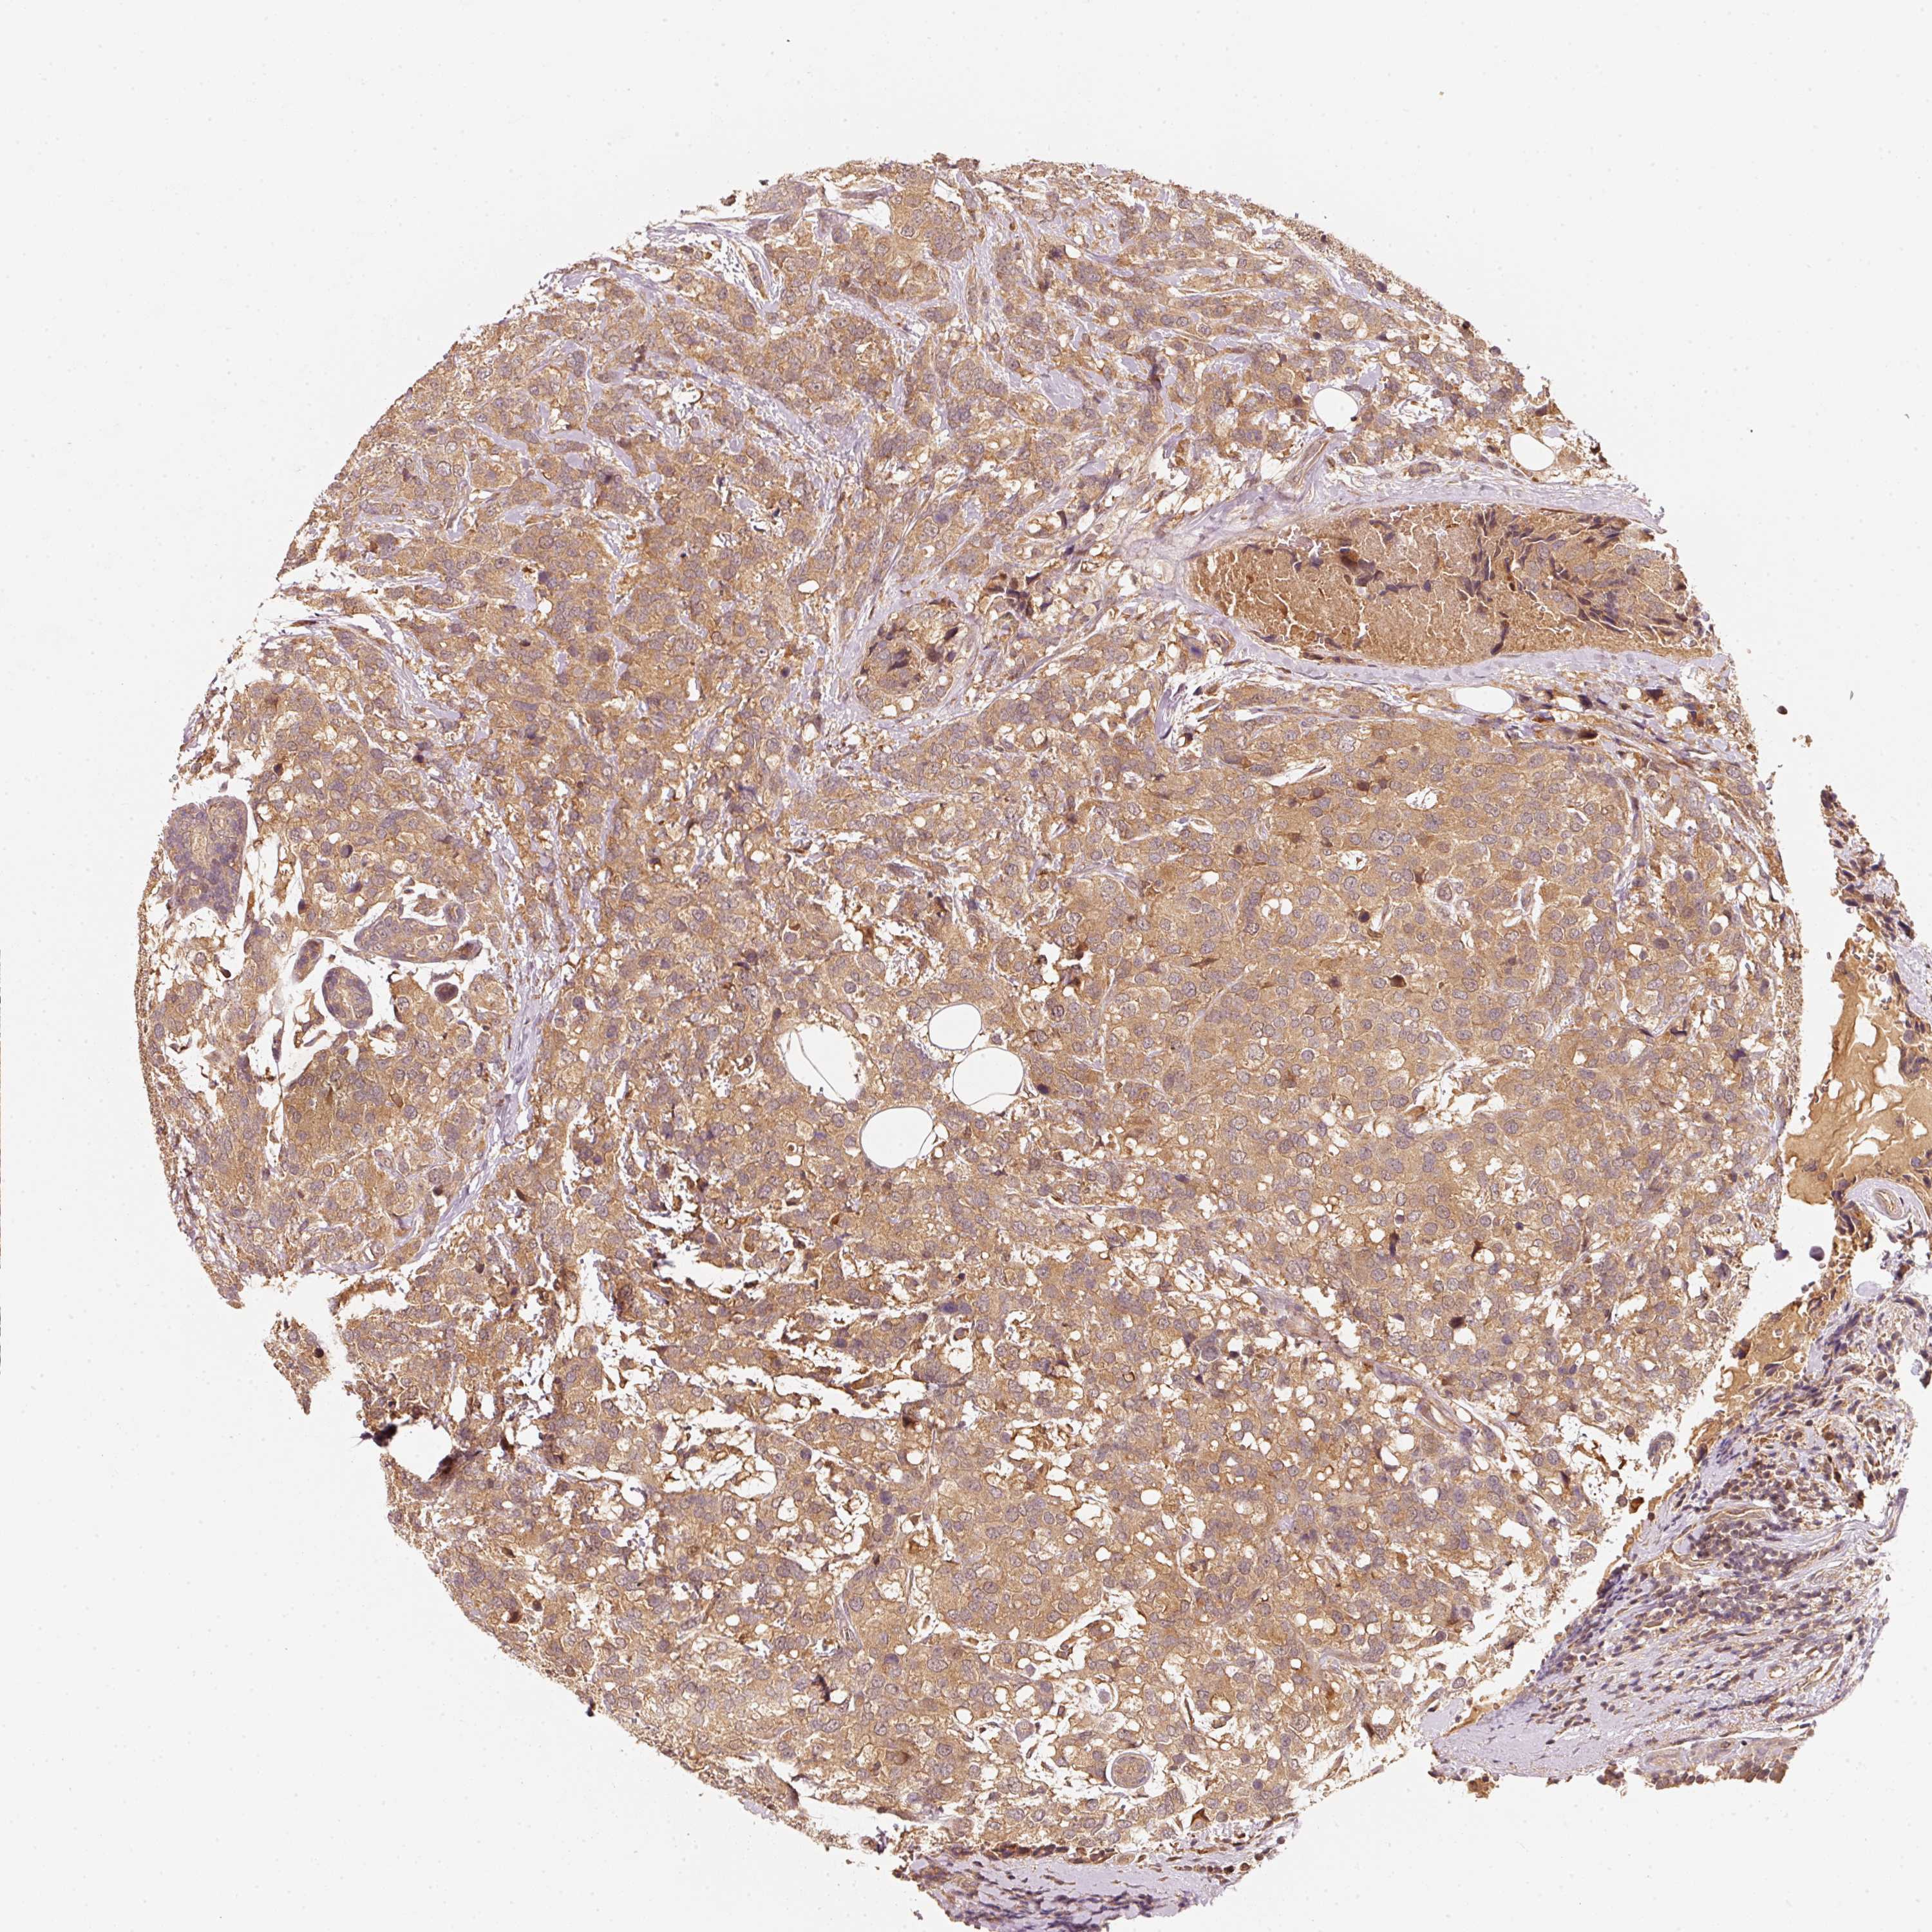

CANCER BREAST CANCER Show tissue menu

BRCA TCGA BRCA VALIDATION PROTEIN EXPRESSION